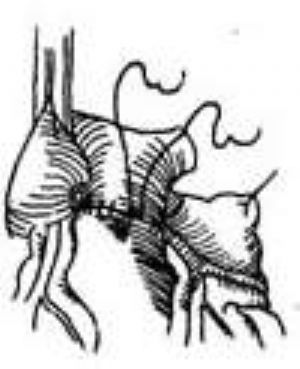

(1)異位起源左冠狀動脈移植入升主動脈術:胸骨正中切口,建立體外循環後,遊離肺總動脈。在靠近肺動脈瓣上方橫向切開肺動脈前壁,顯露左冠狀動脈開口,將左冠狀動脈開口連同開口周圍一部分肺動脈壁一起切下,然後橫向切斷肺動脈,遊離左冠狀動脈近段,在升主動脈根部切開一小窗口,將遊離的左冠狀動脈開口及其四周肺動脈壁與升主動脈根部小切口作端側吻合術,再直接縫合肺動脈切端(圖1)。這種手術設計合理,符合正常生理要求,治療效果良好;但如左冠狀動脈長度不足,移位植入升主動脈後張力過大,則需改用其他手術方法。

(2)切下左冠狀動脈

(4)吻合完成

(5)縫合肺動脈